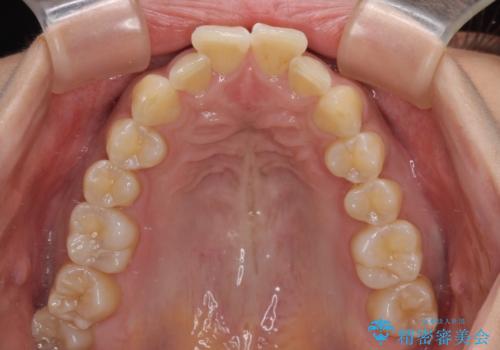

下顎前歯がデコボコしており、その影響で上顎前歯が前方に押し出されている状態でした。

上下左右の親知らずを抜歯し、上下ともに歯列を後方と側方に拡大し、口元を突出させることなくデコボコを解消することとしました。

前歯の形が台形であり、歯列が整ったところでブラックトライアングルが目立つ仕上がりとなったため、IPR(歯と歯の間を削る処置)によって歯の形態を修正し、隙間の目立たない歯列に仕上げることができました。